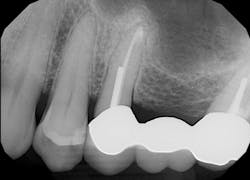

The patient, a 63-year-old female, presented for an emergency visit. She explained her situation, complaining of pain and a lump on the top-left quadrant of her mouth. After an oral evaluation and x-ray (figure 1), it was discovered that she had a large draining granuloma with swelling in the mucobuccal fold near teeth Nos. 12–14 due to a chronic periapical abscess (figure 2).

After using a round burnisher and blow test to determine that there was no perforation to the sinus and the membrane was still intact, the laser was used at a spot size of 1.25 mm, on low power mode, and without mist or air to debride the medial superior area of the bony defect. X-rays were taken following immediate placement of bone-graft material to display the site after using Solea to remove bone and granulation tissue (figures 6 and 7). The entire procedure, including the bone graft, took approximately 40 minutes from start to finish.

During post-op visits, final results at the three- and eight-month marks and x-rays taken at eight months revealed optimal outcomes that met the clinical objective (figures 8–10).